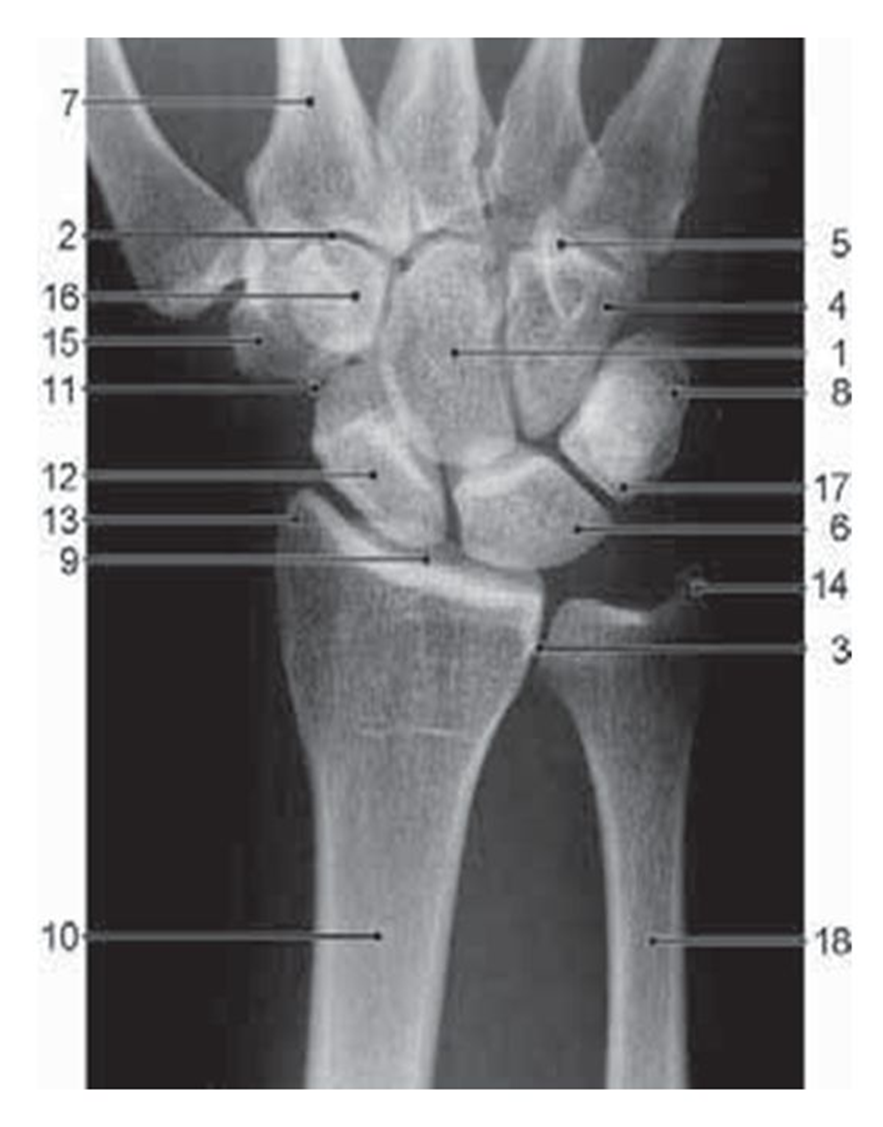

What view is this

PA wrist

What is 1

capitate

What is 16

trapezoid

What is 15

trapezium

What is 12

scaphoid

what is 6

lunate

what is 17

triquetrum

what is 8

pisiform

what is 18

ulna

what is 10

radius

what is 4

hamate